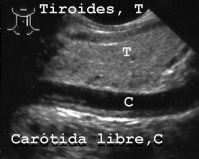

La carótida se observa siempre, esté libre (Fig 27)

27CAROTL.JPG (13492 bytes)

Fig 27